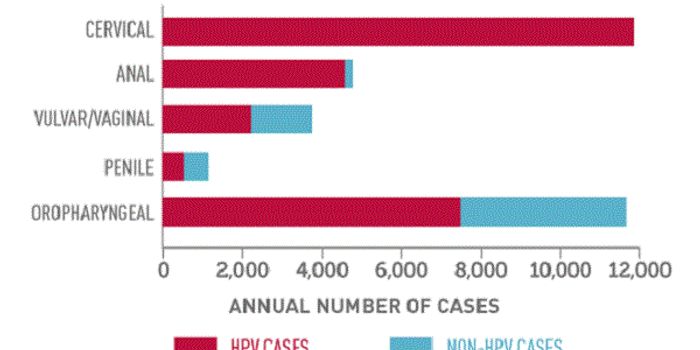

APR 15, 2015Health & MedicineMaking the decision to move from co-testing to primary Human papillomavirus (HPV) screening was one thing. Implementing ...

FEB 16, 2016Clinical & Molecular DXThe American College of Obstetricians and Gynecologists (ACOG) recently revised and updated its recommendations for cerv ...

FEB 02, 2018Clinical & Molecular DXHave you checked your tonsils for human papillomavirus (HPV) lately? A new study raises concerns that the virus could be ...